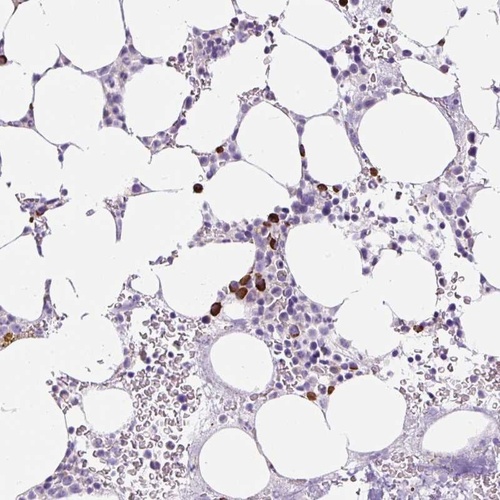

Immunohistochemical staining of human bone marrow shows strong cytoplasmic positivity in hematopoietic cells.